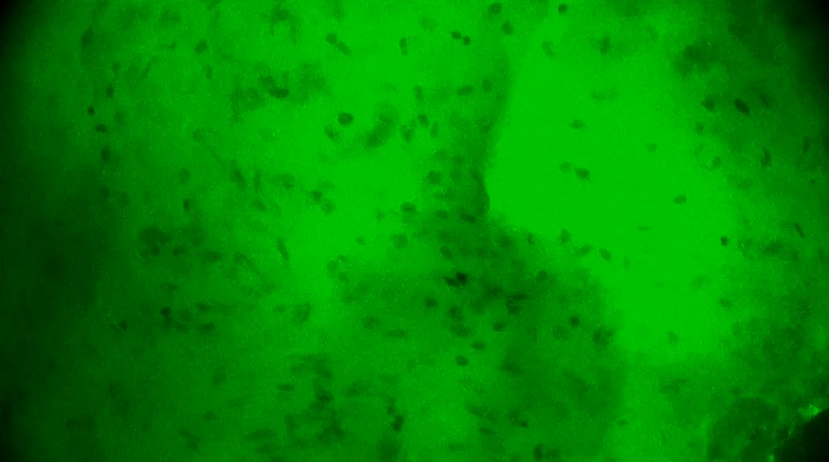

術(shù)中EndoSCell?細(xì)胞圖像如下:

第3次掃查瘤腔,細(xì)胞核分布規(guī)則,無異型性,陰性。